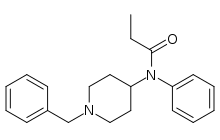

Anilidopiperidines

- 3-Allylfentanyl

- 3-Methylfentanyl

- 3-Methylthiofentanyl

- 4-Phenylfentanyl

- Alfentanil

- α-Methylacetylfentanyl

- α-Methylfentanyl

- α-Methylthiofentanyl

- Benzylfentanyl

- β-hydroxyfentanyl

- β-hydroxythiofentanyl

- β-Methylfentanyl

- Brifentanil

- Butyrfentanyl

- Carfentanil

- Fentanyl

- Lofentanil

- N-Methylcarfentanil

- Mirfentanil

- Ocfentanil

- Ohmefentanyl

- Parafluorofentanyl

- Phenaridine

- R-30490

- Remifentanil

- Sufentanil

- Thenylfentanyl

- Thiofentanyl

- Trefentanil

Structures